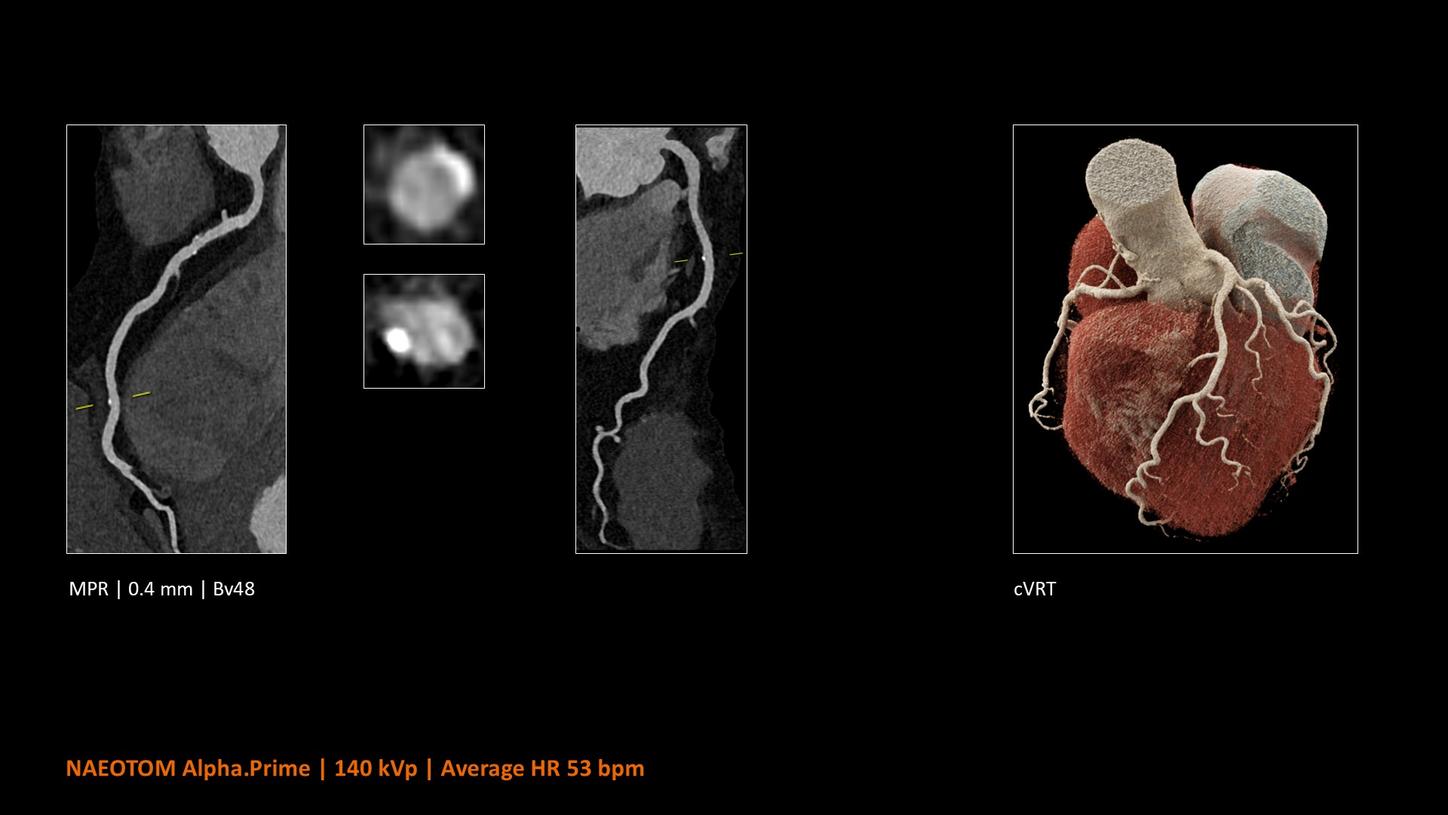

NAEOTOM Alpha® con Quantum Technology®, la nostra nuovissima Dual Source photon-counting CT, offre immagini Quantum HD Cardiac con uno spessore di slice di 0,2 mm. In questo modo è possibile visualizzare dettagli del cuore precedentemente non rilevabili senza incrementi di dose. Inoltre, le informazioni spettrali sono automaticamente disponibili in ogni scansione grazie a un processo di conversione diretta che trasforma i singoli fotoni dei raggi X in un segnale elettrico per creare l'immagine.

Il Dott. Bálint Szilveszter, MD, PhD, presso la Semmelweis University a Budapest, in Ungheria, condivide I benefici dell’elevata risoluzione spaziale e della valutazione della placca con la TC photon counting e come questi permettano una maggior confidenza diagnostica nella valutazione dei disturbi alle coronarie (CAD)